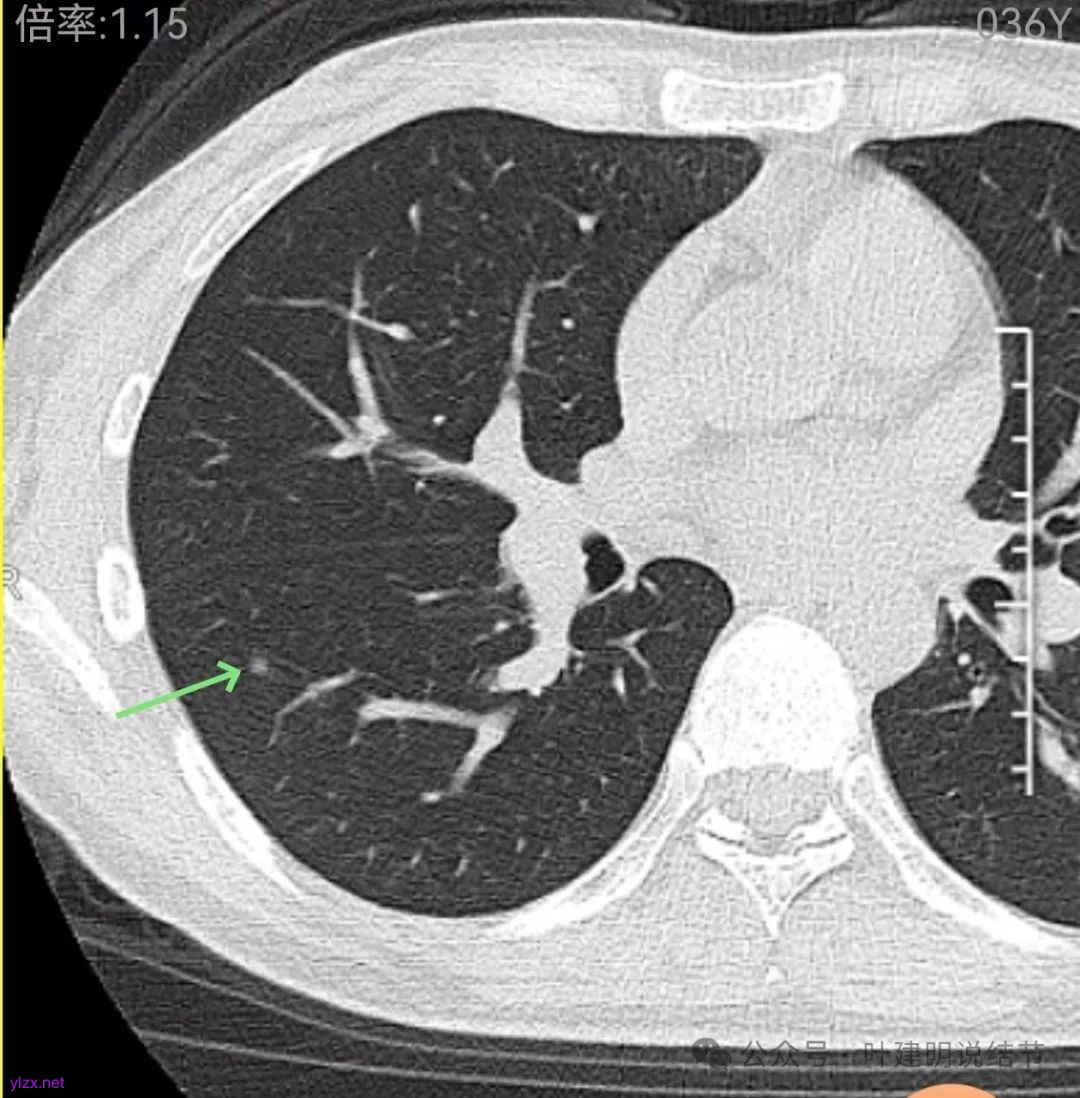

右下当时是很淡的,也显偏模糊的磨玻璃影。

怎么有个点状密度较高的结节在?与上面那截图的淡磨并不完全在一块的。

密度甚高,边界与轮廓清楚,只看这真的不像恶性些。

边缘区也瘤肺界限稍糊,整体轮廓还行。有进展的是不是就是淡磨那处?

两肺多发结节,左侧黄色标注的考虑是肺泡上皮增生可能性大;蓝色的考虑肺泡上皮增生或者少许慢性炎可能性大;右侧红色宽起来并带有红色箭头的这处是主病灶,偏混合密度,整体轮廓较为清楚,边缘显得毛糙,从2024年12月份的来看,要考虑是肿瘤范畴,原位癌或者微浸润性腺癌可能性较大,也不能完全排除不典型增生。但是在2022年的时候,这个病灶的边上也有一个实性的微小结节,如果只看2022年的,这么小的实性结节,又比较圆,表面也显得较为光滑,是要考虑良性的,当然太小了需要动态观察。回头再重新来看2024年底的,发现绿色箭头所指的这个微小实性的较2022年几乎没有变,去仔细寻找2022年的,发现当时在实性结节旁边也有密度很淡的一点磨玻璃影(也可能真的就是一处,只是扫描不够薄,密度的变化有些突兀而已),而到了2024年12月份,实性微小这处没有明显变化,但是原来很淡的磨玻璃变成了混合磨玻璃,范围也明显扩大。所以总体来看右肺下叶这处是考虑恶性的,而且从磨玻璃结节角度来讲,还是生长比较快的,就是说还是有一定风险的。加上左侧还有两处也是磨玻璃持续存在,虽然边缘轮廓显模糊一点,但多年以后也可能仍然要变成原位癌或者微浸润性腺癌之类的东西。通盘考虑以后,我倾向于右侧近期单孔胸腔镜下微创局部切除,左侧随访观察,等到有进展并风险增加再来考虑处理。意见供参考!